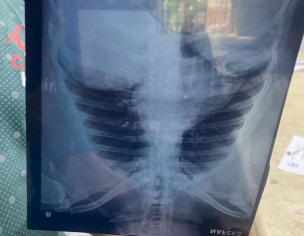

He got paralysis attacked in the morning, he was moved to hospital and as per dr he has 0 surviving chance, need opinion and what are treatment should he be given to get a life

Attach Photo here: